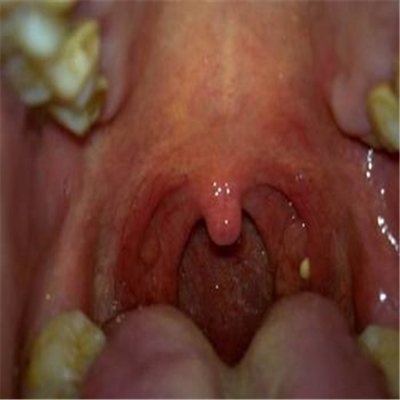

扁桃體惡性腫瘤圖片

扁桃體癌圖 (64)

扁桃體癌圖 (65)